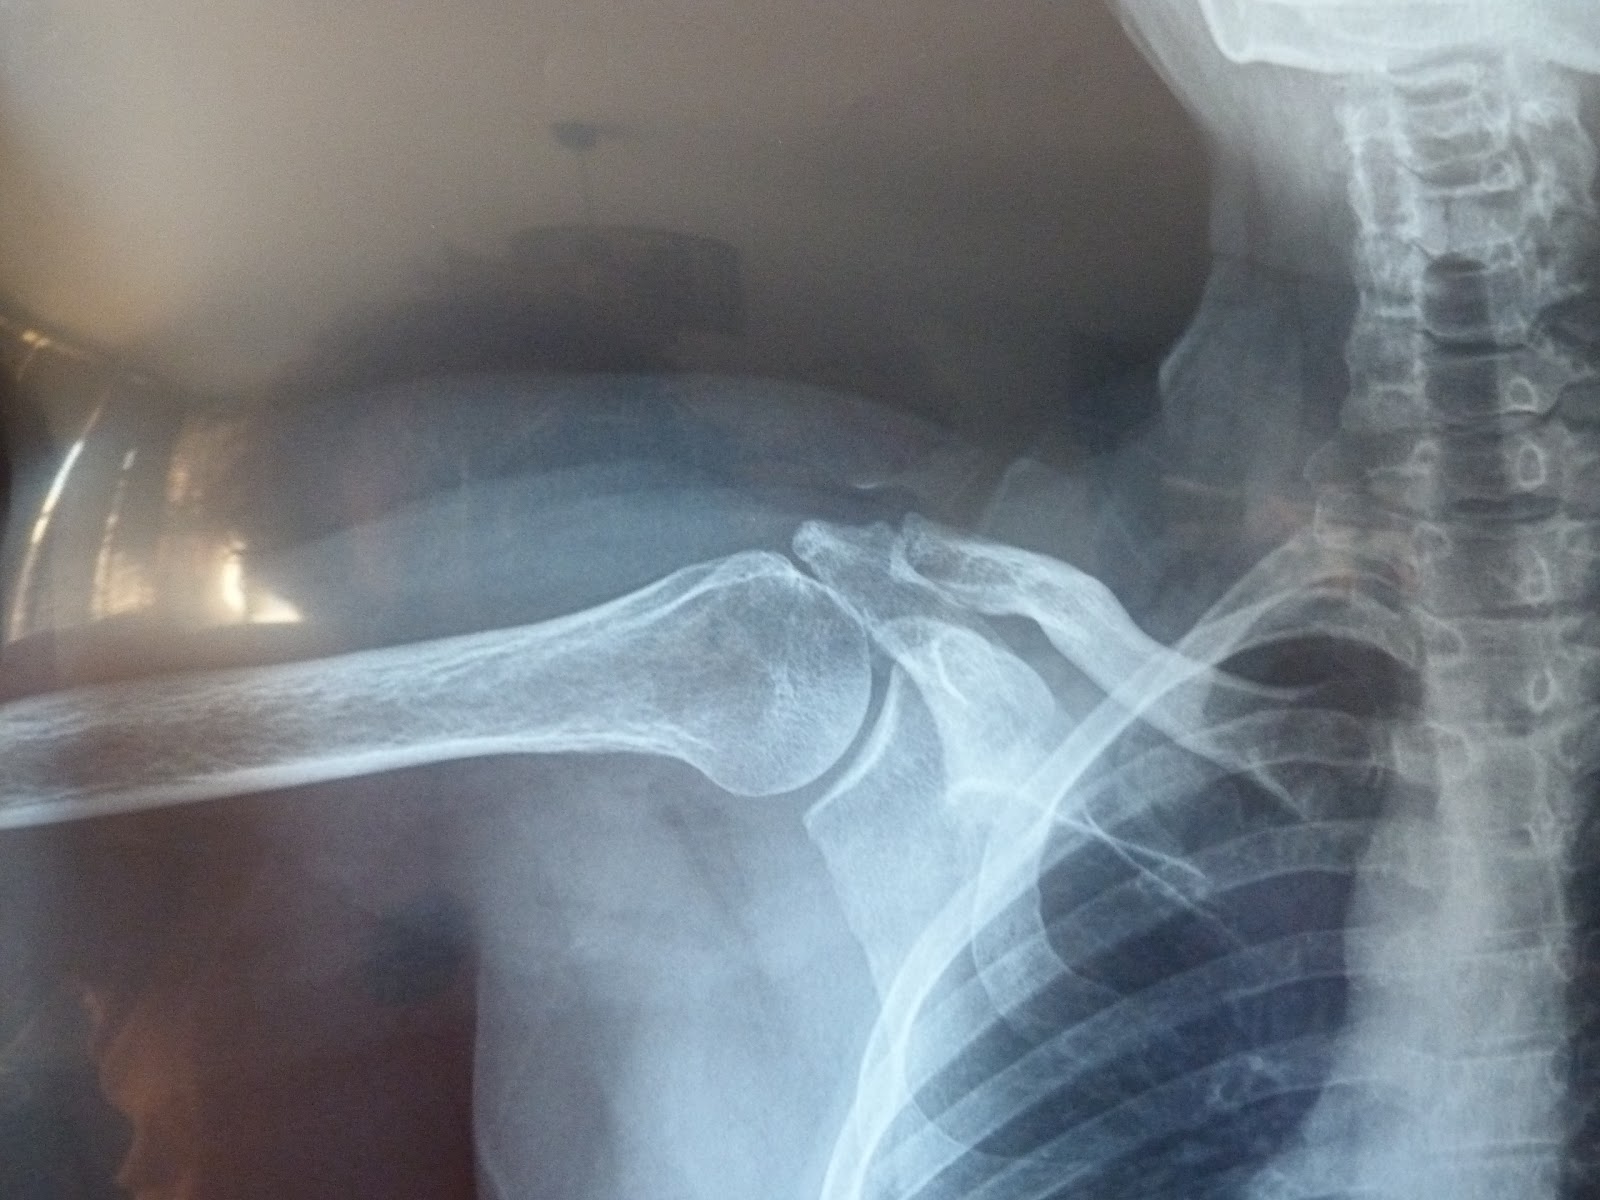

Incapacidad Permanente Total Por Rotura Supraespinoso, , , , , , , 0, ¿PORQUÉ SE ROMPE EL SUPRAESPINOSO CON LA EDAD? - Fidias, fidias.net, 960 x 720, jpeg, WebINCAPACIDAD PERMANENTE TOTAL PARA LA PROFESIÓN HABITUAL. SITUACIÓN DE SEGUNDA ACTIVIDAD. PENSIÓN DE INCAPACIDAD. El demandante que tiene., 20, incapacidad-permanente-total-por-rotura-supraespinoso, Novedades y Muebles WebINCAPACIDAD PERMANENTE TOTAL PARA LA PROFESIÓN HABITUAL. SITUACIÓN DE SEGUNDA ACTIVIDAD. PENSIÓN DE INCAPACIDAD. El demandante que tiene.

WebLos Juzgados Reconocen Incapacidad Total por Síndrome Subacromial ¡Nuevo éxito! Se estima nuestra demanda por incapacidad permanente total por Síndrome Subacromial. WebIncapacidad por tendinitis del supraespinoso. La mayor parte de las personas que sufren de este tipo de dolencias suelen ser reacias a estar incapacitados. Habitualmente y en. WebIncapacidad permanente total por rotura supraespinoso Clasificación de la discapacidad del manguito de los rotadores El hombro está formado por tres huesos: el.